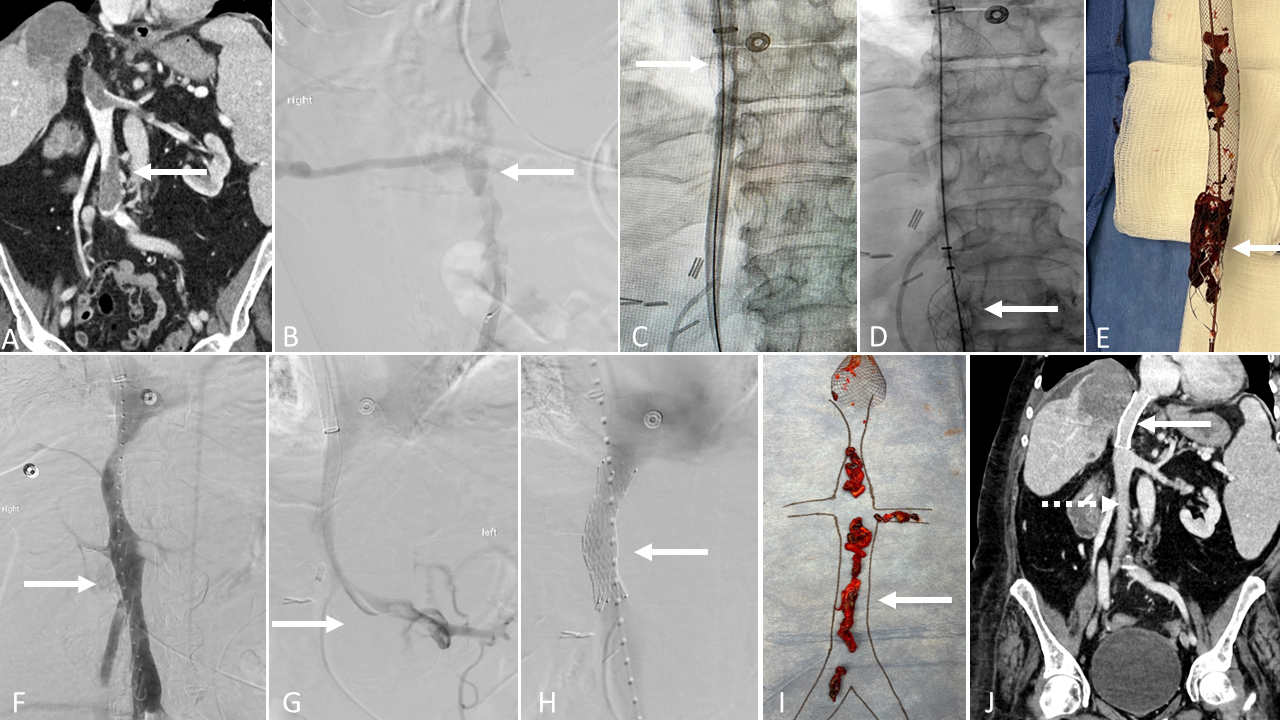

A 57-year-old female with recently diagnosed stage IVB cervical cancer post chemotherapy (cisplatin/paclitaxel/bevacizumab) presented with right lower extremity pain and swelling for >5 days. Venous duplex examination of the right lower extremity demonstrated acute occlusive thrombus throughout the right external iliac vein, common femoral vein, femoral vein, and popliteal vein. CT venography of the abdomen and pelvis demonstrated a large necrotic cervical mass (A; solid arrow) with metastatic lymphadenopathy as well as chronic thrombus throughout the right iliocaval and iliofemoral venous segments and left renal vein (A; dashed arrow).

The patient was placed supine, and general anesthesia was administered per institutional preference. Access to the right popliteal vein was obtained, and a sheath was placed. Right lower extremity ascending venography was performed, demonstrating acute occlusive thrombus (B).

A wire and catheter were navigated into the IVC. Access to the right IJ vein was obtained, and the 20F Protrieve sheath was placed. The device funnel (C) was deployed in the patent suprahepatic IVC.

From the right popliteal access, the ClotTriever thrombectomy catheter (D) was used to make 3 thrombectomy passes of the IVC, right iliocaval, iliofemoral, femoral, and popliteal veins. Completion right lower extremity ascending venography demonstrated removal of acute occlusive thrombus with brisk in-line flow (E).

There was extrinsic compression of the right common iliac and external iliac veins for which a 14-mm x 80-mm Abre stent (F) was placed. Post-deployment angioplasty was performed with a 12-mm balloon.

Access to the left common femoral vein was obtained, and a sheath was placed. A wire and catheter were navigated into the left renal vein. Left renal venography demonstrated non-occlusive thrombus (G; solid arrow), and the Protrieve sheath was left in place (G; dashed arrow).

From the left common femoral vein access, the InThrill thrombectomy catheter (H) was used to make 3 thrombectomy passes of the left renal vein. Completion left renal venography demonstrated removal of acute occlusive thrombosis with brisk in-line flow (I; solid arrow). The Protrieve sheath was removed, and hemostasis was achieved.

At the conclusion of the procedure, thrombus from the right lower extremity thrombectomy (J) and Protrieve sheath (K) had been removed. Swelling improved within 48 hours.

Discussion

Embolic complications from chronic thrombus, which is unlikely to respond to anticoagulation or thrombolysis, pose risks of cardiopulmonary compromise and may necessitate additional invasive procedures. The 20F Protrieve sheath funnel diameter of 33.5 mm provides atraumatic caval wall apposition and was utilized in this case to perform rapid removal of thrombotic material via a large-bore manual aspiration mechanism, similar to the FlowTriever System.